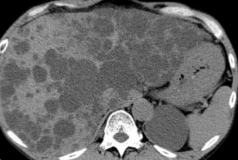

Polycystic liver disease. Red arrow. Infected hepatic cyst (Courtesy Dr. V. Penopoulos)